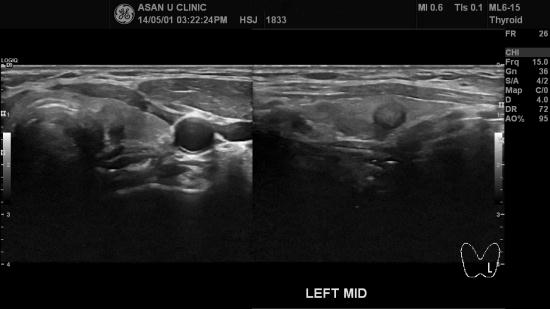

아산유외과 개원 후 23번째 갑상선암 진단.

유방암으로 수술후 시행한 PET 검사에서 갑상선에 이상이 있다고

의뢰되신 72세 여성분입니다.

좌엽 갑상선에 1cm미만의 매우 작은 혹이 있어

세포검사하여 갑상선의 유두암 진단되었습니다.

크기도 작아 완치율은 유방암보다 훨씬 높습니다.